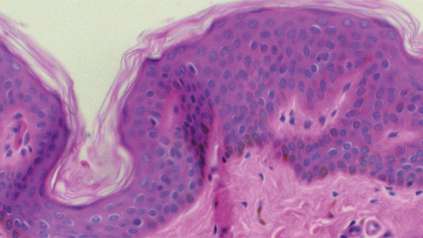

At the Wellcome Genome Campus we undertake both wet and dry lab science, basic research and the delivery of bioinformatics resources for the global scientific community.